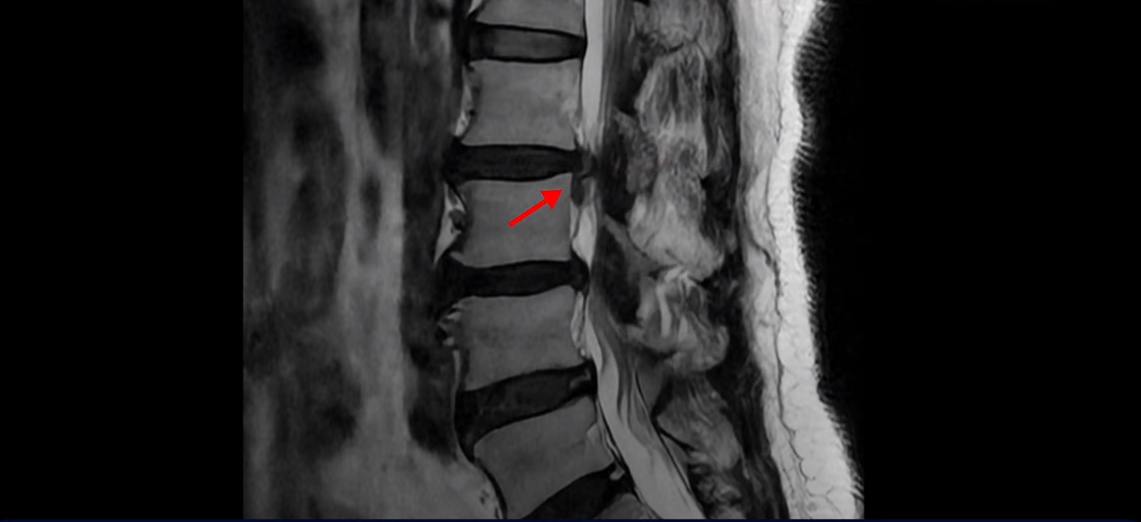

이분 MRI 보시면 2번 3번, 3번 4번이 두 마리가 특히 안 좋습니다.

2번 3번에는 우선 디스크가 파열되어 흘러내려 있습니다. 이 디스크는 파열된 지 오래된 걸로 보입니다.

이 마디는 중심성 협착도 있어서 허리 신경 공간이 많이 좁아져 있습니다.